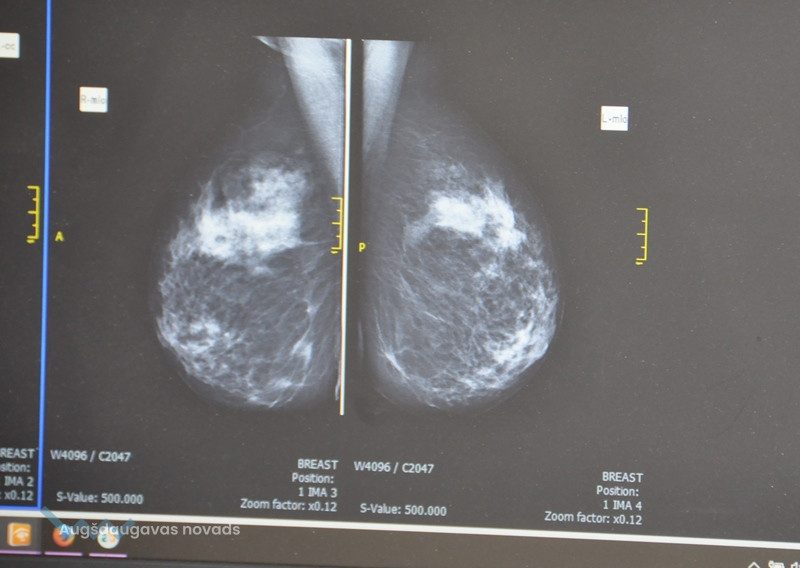

Arī šogad darbu turpina Daugavpils reģionālās slimnīcas mobilais mamogrāfs (īpaši aprīkots autobuss sievietes krūšu pārbaudei), kas izbraukumos pacientiem sniedz iespēju saņemt augstvērtīgu mamogrāfijas izmeklējumu dzīvesvietas tuvumā. No augusta līdz oktobrim mamogrāfs būs pieejams Daugavpils novada desmit pagastos.

Mamogrāfs brauc gan uz lielākiem, gan mazākiem ciemiem, lai  ikvienai sievietei pakalpojums būtu pēc iespējas pieejamāks. “Mūsu rīcībā diemžēl nav kopējās statistikas par atklātajiem ļaundabīgajiem audzējiem, mums ir dati tikai par sievietēm, kuras pēc mūsu pārbaudes tiek sūtītas uz papildus izmeklējumiem. Tā ir apmēram trešā daļa no visām sievietēm. Tas ir ļoti daudz. Diemžēl no tām daudzām ir onkoloģija, kas ir ārkārtīgi izplatīta slimība,” norāda J.Ņikitina.

Radiologa asistente Janīna Ņikitina aicina sievietes atbildīgi izturēties pret savu veselību un vismaz vienu reizi divos gados pārbaudīt savas krūtis. Mamogrāfija ir domāta sievietēm virs 40 gadu vecuma, savukārt jaunākām ir ieteicama ultrasonogrāfija. “Nav jābaidās pārbaudīties, jo bailes ir slikts palīgs. Vienreiz divos gados ir jānāk uz profilaktisko pārbaudi, jo veselība ir mūsu personīgā bagātība. Mašīna un māja nav bagātība, jo to var nopirkt, bet veselību par naudu nenopirksi,” mudina mediķe. “Ir nepatīkami, ja sievietei kaut ko atrod, bet labāk šo problēmu sākt risināt pēc iespējas ātrāk, jo pati par sevi tā nekur nepazudīs. Daudzas sievietes krūts audzējus “ielaiž”, lai gan sieviete pati var saskatīts izmaiņas – ievilktus krūtsgalus, cietus, sāpīgus bumbuļus krūtīs utt. Faktiski, poliklīnika brauc pie sievietēm uz mājām, tāpēc ir grēks neizmantot šādu izdevību.”